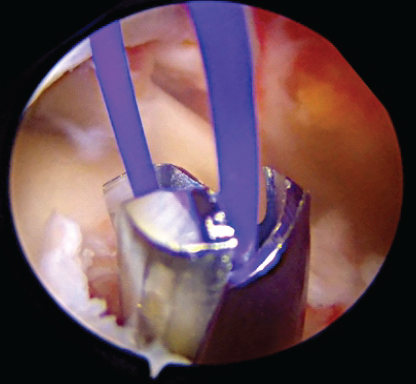

Over this beath pin, a 4.5 mm cannulated reamer is meticulously utilized to create a bone tunnel, through which a Prolene shuttle loop is subsequently passed and retrieved into the joint, facilitating suture management (Fig. 3 and 4).

Figure 3: Beath pin exiting at humerus ridge.

Figure 4: Prolene loop shuttle.